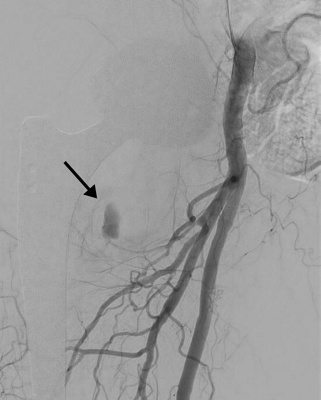

Embolisation einer Nachblutung nach Implantation einer Endoprothese an der rechten Hüfte

embolisation2